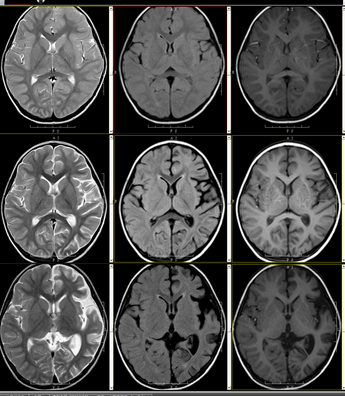

Rasmussen 脑炎患者的MRI 影像评价:评估MRI 影像中显示的脑萎缩和灰质信号改变情况以及以上改变在随访MRI 检查中的进展情况,评价脑萎缩包括皮层萎缩的部位和范围、外侧裂、局部脑沟变化情况、患侧侧脑室体部位大小及与对侧比较、颞角大小及与对侧比较。脑沟、脑裂、脑室增宽的评价以健康侧脑沟、脑裂、脑室为标准,增宽<25%为轻度,增宽在25%~50%为中度,增宽>50%为重度。

Rasmussen 脑炎是一种发病原因尚不十分明确罕见疾病。1958 年,加拿大神经病学研究者西奥多·拉斯穆森(Theodore Rasmussen)及其同事首先发现了3 例由慢性局灶性脑炎所致的局灶性癫痫病,当时他们根据该病脑组织标本在病理学上的表现,认为该病可能是由病毒感染引起。之后很多学者应用原位杂交PCR 方法研究发现了肌细胞病毒和单纯疱疹病毒在Rasmussen 脑炎中呈阳性表达,因此因为病毒感染可能与Rasmussen 脑炎发病相关,相关流行病学研究也显示该病与病毒感染有关。但后来一些研究发现:“并不是所有的Rasmussen 脑炎患者组织标本中都存在病毒感染。”近年来有研究证实,Rasmussen脑炎并不是由单纯的病毒引起,病毒感染后的免疫反应也是该病发病的重要机制。Rasmussen 脑炎患者的MRI 影像特点主要有患侧侧脑室体部和颞角扩大、外侧裂和局部脑沟增宽、脑回变小、壳核和尾状核萎缩,这与病理学检查结果基本上一致,与前人的相关研究基本一致。另外,Rasmussen 脑炎患者的MRI 影像还实现,灰质区和白质区T2WI 和FLAIR 系列呈高信号,T1WI 系列呈不均匀低信号。随着病变的进展,MRI 影像可见病变侧半球萎缩性改变加重和范围扩大,皮层信号改变较大,可以较好的显示病变进行,可为预后评估提供较多的参考信息。

患者2014-11-7、1014-11-21住院头颅MR检查,后2015-3-21门诊返院头颅MR检查,图像先后如下: